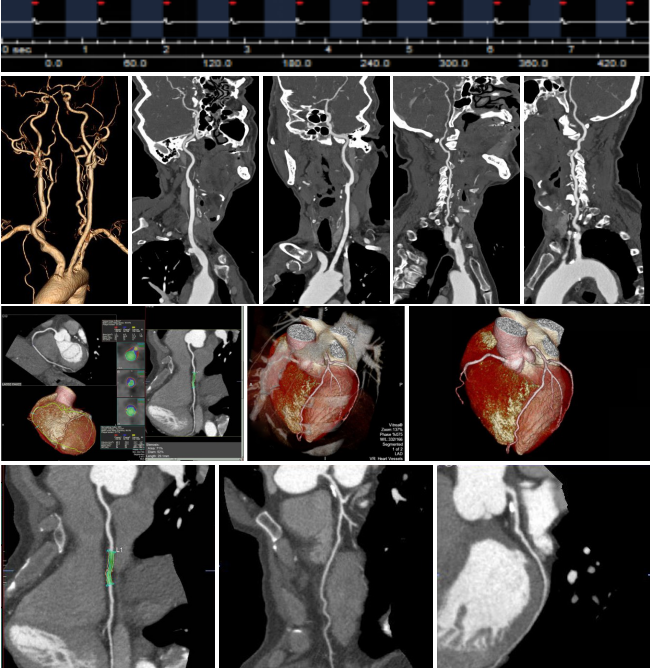

病例一 女,71歲,反復(fù)發(fā)作心慌、 胸悶、 出汗,血糖2 . 56 mmol/ L。

免疫組化:

CEA(-),CD31:血管內(nèi)皮細(xì)胞(+),Ki67:約1%瘤細(xì)胞陽(yáng)性,CK8(+),CK19(+),S yn(+),CgA(+)。

動(dòng)脈期可見(jiàn)胰腺體尾部腫瘤明顯強(qiáng)化,CT-MIP圖可見(jiàn)供腫瘤血血管,VR圖像可清晰顯示腫瘤的供血血管以及與周圍組織的關(guān)系。 術(shù)后結(jié)果為胰腺體尾部胰島素瘤。

病例二 女,63歲,以持續(xù)性腹部疼痛不適半天就診。既往有冠心病15年、心房纖顫史5年余;高血壓5年。

采用心臟+主動(dòng)脈血管一站式檢查,可見(jiàn)該患者腸系膜上動(dòng)脈及其分支充盈缺損,同時(shí)顯示左心耳內(nèi)多發(fā)血栓, 隨時(shí)有血栓脫落的危險(xiǎn)。

全麻下行剖腹探查、 腸系膜上動(dòng)脈血栓取出術(shù), 病理顯示血栓樣組織機(jī)化。

患者術(shù)后第三天,由于右側(cè)肢體活動(dòng)障礙,語(yǔ)言受限,急查CT發(fā)現(xiàn)多發(fā)腔隙性腦梗塞,MRI檢查后明確左側(cè)急性梗死。

腸系膜上動(dòng)脈栓塞栓子多來(lái)源于心臟,也可來(lái)自于主動(dòng)脈壁粥樣硬化斑塊脫落。腸系膜上動(dòng)脈從腹主動(dòng)脈分出,主干口徑又較大,脫落的栓子易于進(jìn)入,在血管狹窄或分叉處導(dǎo)致血管栓塞。

臨床表現(xiàn)主要有“Bergan三聯(lián)征”1 、劇烈而沒(méi)有相應(yīng)體征的腹痛。2器質(zhì)性心臟病和并發(fā)心房纖顫的心臟病。3、胃腸排空障礙表現(xiàn)如腹瀉、 血便。

640層寬體探測(cè)器CT掃描速度快,可進(jìn)行大范圍心血管一站式檢查,快速排除血管病變,且由于探測(cè)機(jī)單元只有0.5mm,對(duì)于一些微小的病變也能清晰顯示。

病例三 男,54歲,10小時(shí)前無(wú)明顯誘因突然出現(xiàn)右側(cè)胸背部疼痛,呈脹痛,伴有大汗、頭暈癥狀。

腹盆腔CT腸道充氣成像可見(jiàn)橫結(jié)腸脾曲結(jié)腸癌, 升結(jié)腸及降結(jié)腸多發(fā)息肉

腹腔鏡見(jiàn)腹腔粘連較重, 轉(zhuǎn)開(kāi)腹手術(shù), 取左側(cè)腹直肌切口, 逐層進(jìn)腹, 于橫結(jié)腸脾曲觸 及一腫塊, 遂行左半結(jié)腸切除術(shù)。

640層寬體探測(cè)器CT掃描速度快, 掃描時(shí)間只用了2 . 3 s,克服了胃腸道蠕動(dòng)造成的偽影 和漏層, 使腹部圖像質(zhì)量大大提高。 仿真內(nèi)窺鏡的圖像可觀察到黏膜的皺襞 , 不僅可清晰的 顯示小息肉及病變 , 而且可顯示出胃腸道造影及內(nèi)窺鏡易于遺漏的部位。